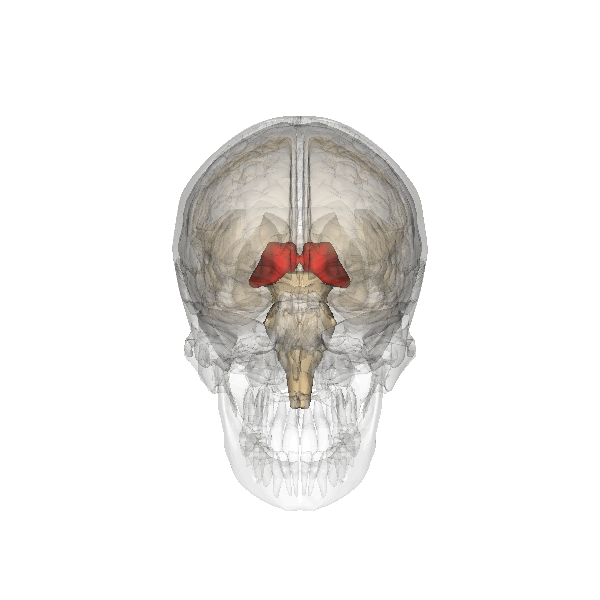

Nuclei

Every nucleus of the thalamus is responsible for the processing of specific information. In humans, the dorsal lateral geniculate nucleus (LGN), medial geniculate nucleus (MGN), ventral posterolateral (VPL) and ventral posteromedial (VPM) are first-order relay nuclei involved in the processing of sensory information.